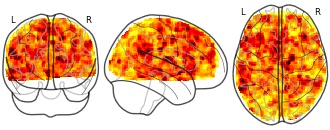

License information was derived automaticallyDescriptionPPI maps for task switch > repeat (local switch cost) bilateral dorsal caudate seed region negatively regressed with behavioral switch cost.

Collection description

Dopaminergic signaling in striatum is strongly implicated in executive functions including cognitive flexibility. However, there is a paucity of multimodal research in humans defining the nature of relationships between endogenous dopamine, striatal network activity, and cognition. Here, we measured dopamine synthesis capacity in young and older adults using the PET tracer 6-[18F]fluoro-L-m-tyrosine, and examined its relationship with cognitive performance and functional connectivity during an fMRI study of task switching. Aging is associated with alteration in dopamine function including profound losses in dopamine receptors, but an apparent elevation in dopamine synthesis. A compensatory benefit of upregulated dopamine synthesis in aging has not been established. Across young and older adults, we found that cognitive flexibility (low behavioral switch cost) was associated with stronger task-related functional connectivity within canonical fronto-striato-thalamic circuits connecting left inferior frontal gyrus, dorsal caudate nucleus (DCA) and ventral lateral/ventral anterior thalamic nuclei. In young adults, functional connectivity mediated the influence of DCA dopamine synthesis capacity on switch cost. For older adults, these relationships were modified such that DCA synthesis capacity and connectivity interacted to influence switch cost. Older adults with most elevated synthesis capacity maintained the pattern of connectivity-cognition relationships observed in youth, whereas these relationships were not evident for low synthesis older adults. Together, these findings suggest a role of dopamine in tuning striatal circuits to benefit executive function in young adults, and clarify the functional impact of elevated dopamine synthesis capacity in aging.

Subject species

homo sapiens

Modality

fMRI-BOLD

Analysis level

group

Cognitive paradigm (task)

task-switching

Map type

T